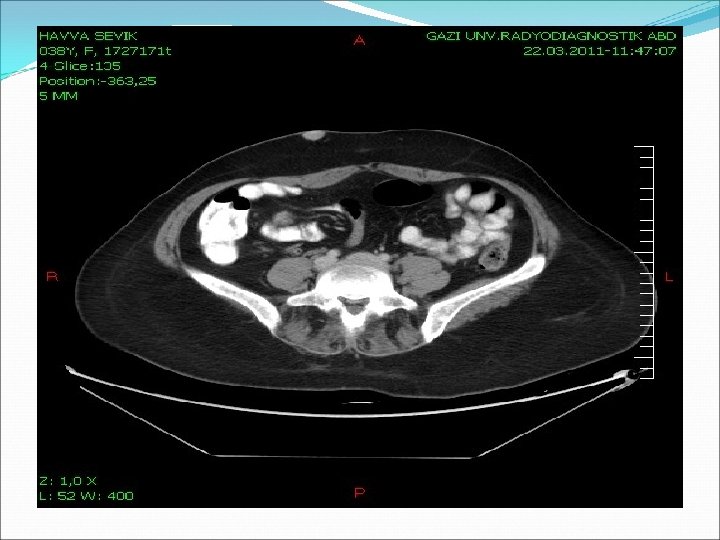

BT (Toraks-abdomen): Direk grafilerde izlenen pseudofraktürler ile uyumlu görünüm mevcut. Sağda karın ön duvarında infraumblikal düzeyde 18 mm boyutunda cilt altında hiperdens nodüler lezyon BOYUN BT: Her iki tiroid lobunda en büyüğü sol tiroid lobunda 12 mm boyutunda hipodens nodüler lezyon.